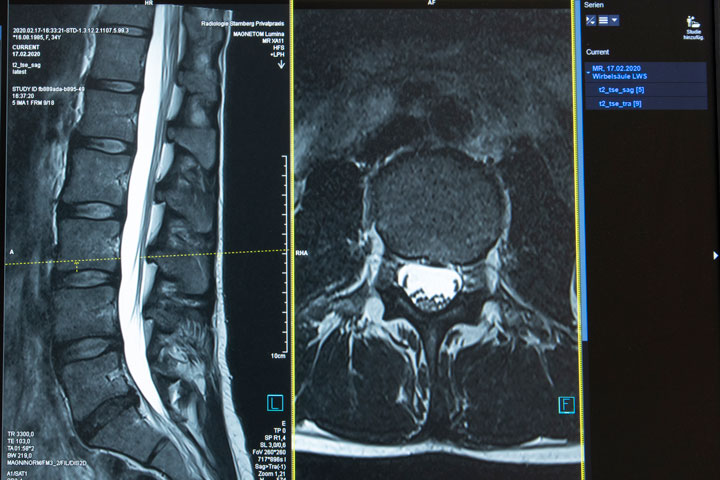

Magnetresonanztomographie (MRT)

Wichtigste Voraussetzung für das Erkennen eines krankhaften Befundes ist eine optimale Bildqualität. Nur so gelingt es auch kleinste Veränderungen, die Beschwerden verursachen (z.B. kleiner Bandscheibensequester, der auf den Nerv drückt) zu diagnostizieren und damit entsprechend korrekt zu behandeln.

Für diese hochauflösende Bildqualität verwenden wir mehrere Komponenten

- 3.0 Tesla Hochfeld-Magnetresonanztomograph SKYRA (48-Kanal), durch die hohe Feldstärke sind auch kleinste Strukturen darzustellen.

- Mehrkanal-Spulensysteme, speziell konstruiert für die einzelnen Organe: (16-Kanal Handgelenk, 16-Kanal Schulter, 15-Kanal Knie-Sprunggelenk, 18-Kanal Brust, 18-Kanal Bauch/Becken) für eine optimale Bildqualität.

- Spezielle Sequenzen (Aufnahmeprotokolle), individuell abgestimmt auf die Beschwerdesymptomatik und Fragestellung, die sich durch eine besonders dünne Schichtdicke und hohe Detailerkennbarkeit auszeichnen